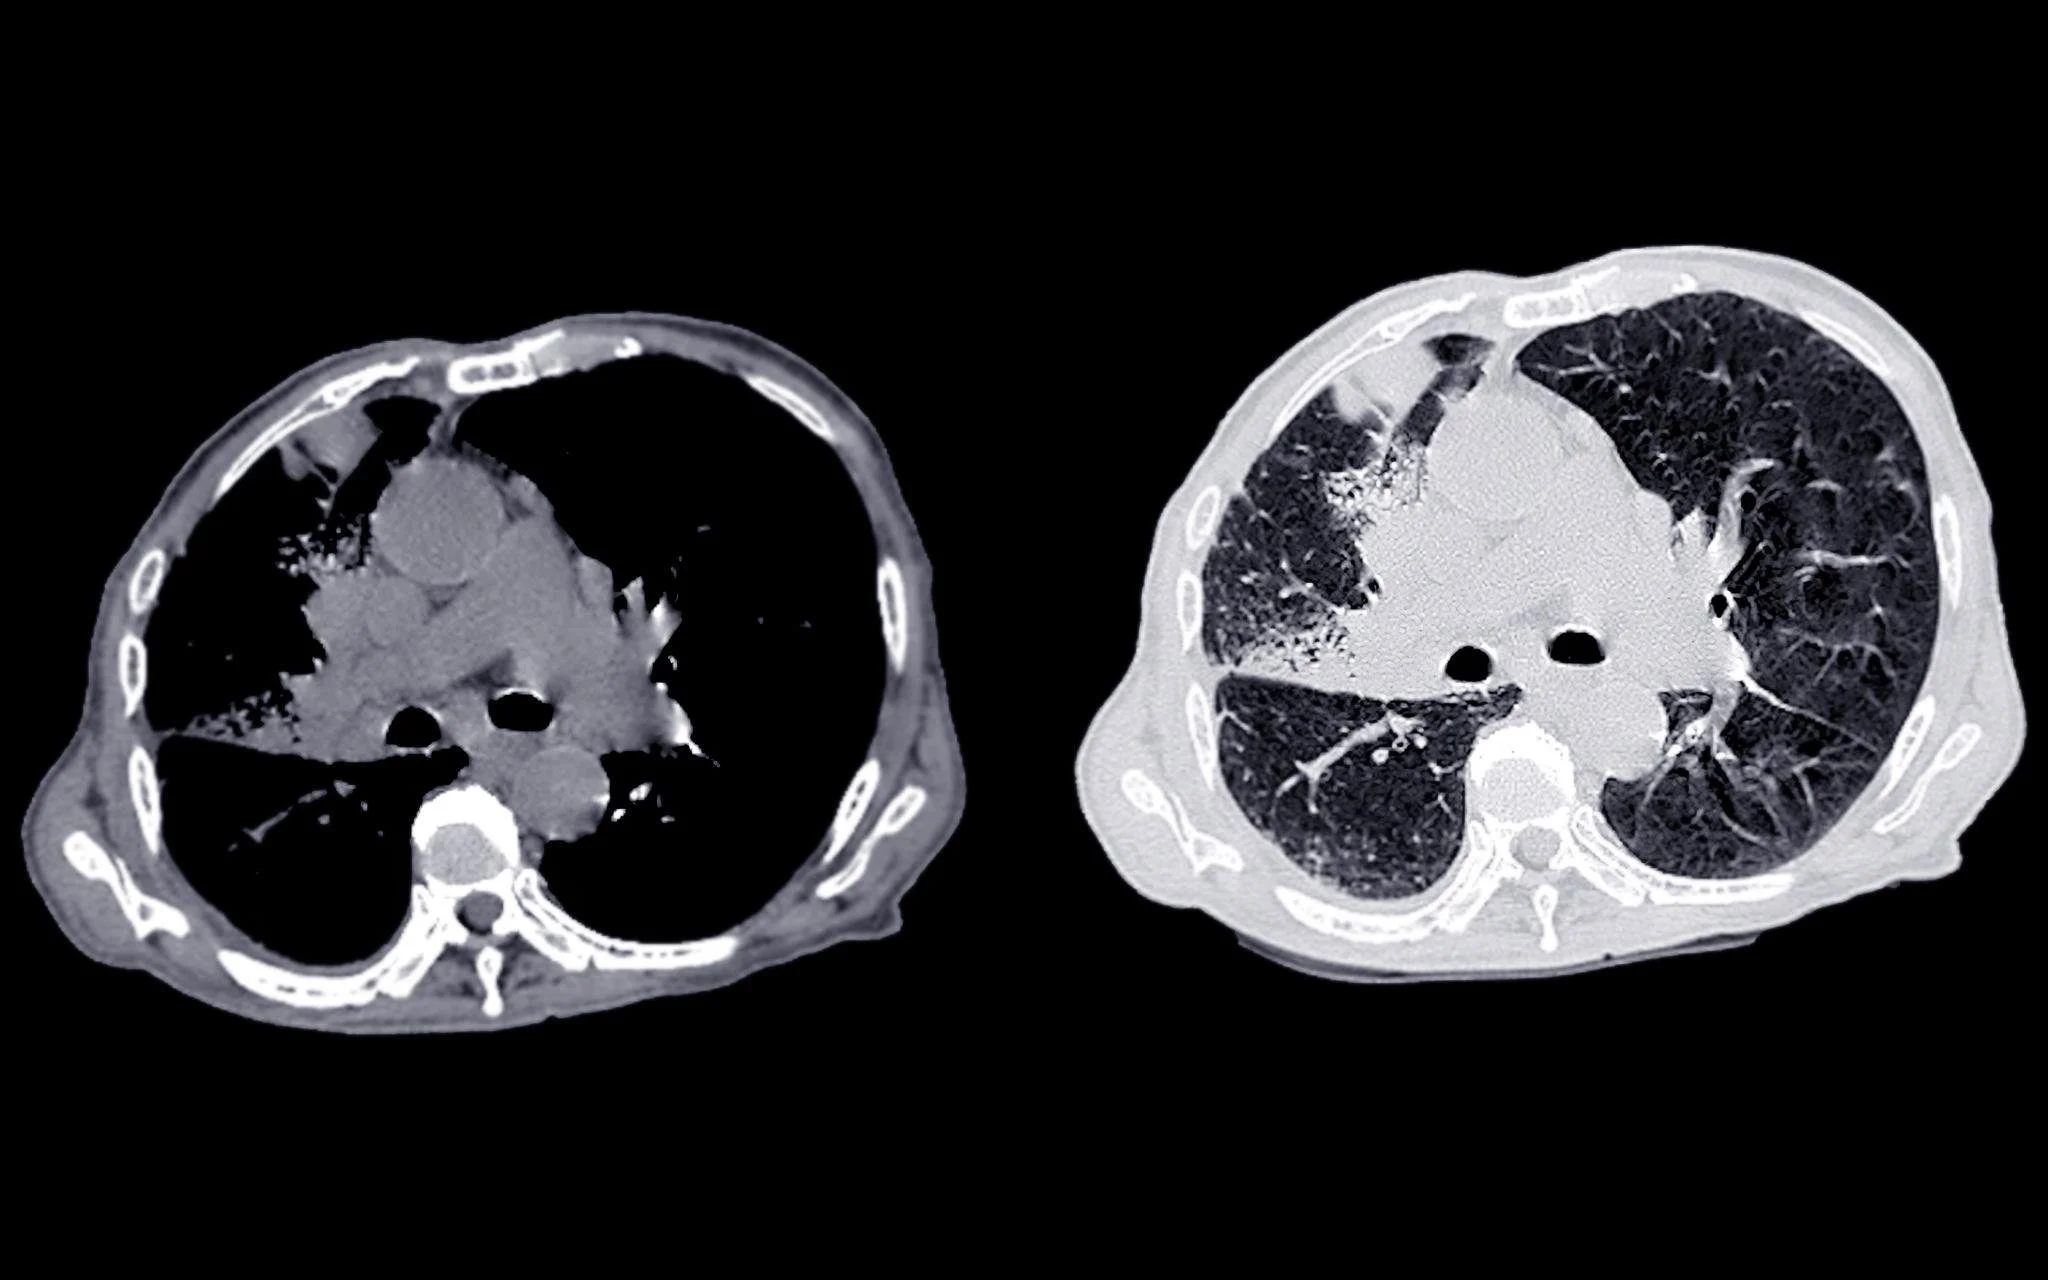

For decades, clinical decision-making has relied heavily on 2D medical imaging; CT scans, MRIs, X-rays, and ultrasound slices viewed on flat screens. These imaging modalities have been essential to diagnosis, treatment planning, and ongoing patient care.

However, as medical cases become more complex and care teams more collaborative, the limitations of viewing three-dimensional anatomy through two-dimensional slices are becoming more apparent. Clinicians are often required to mentally reconstruct depth, spatial relationships, and anatomical complexity from a series of static images.

Traditional 2D imaging remains highly precise and indispensable for diagnostics, but it places a significant cognitive burden on clinicians. Understanding complex anatomy from stacked image slices requires experience, spatial reasoning, and time.

In challenging cases, clinicians must mentally assemble multiple views to interpret:

• The depth and positioning of structures

• The relationship between organs, vessels, and pathology

• The spatial impact of tumors, lesions, or abnormalities

• The procedural approach required for treatment

While experts are skilled at this process, it can still slow interpretation, complicate interdisciplinary discussions, and make it harder to communicate findings clearly to patients and non-specialists.